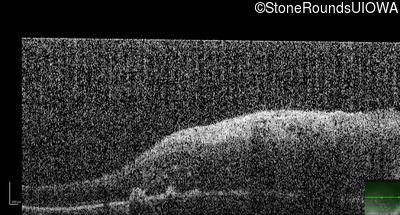

This 9 year old male was noted to have some crossing of his eyes at 2 months of age and the eye exam which followed identified a retinal lesion in the right eye. When he was six years old an epiretinal membrane was noted in his left eye. Two years later it was decided that it was a thin hamartoma in that eye as well. He underwent neuroimaging at age 7 which identified bilateral acoustic neuromas.

| Age at visit: 8 years |

| Age at visit: 10 years |

| Age at visit: 11 years |